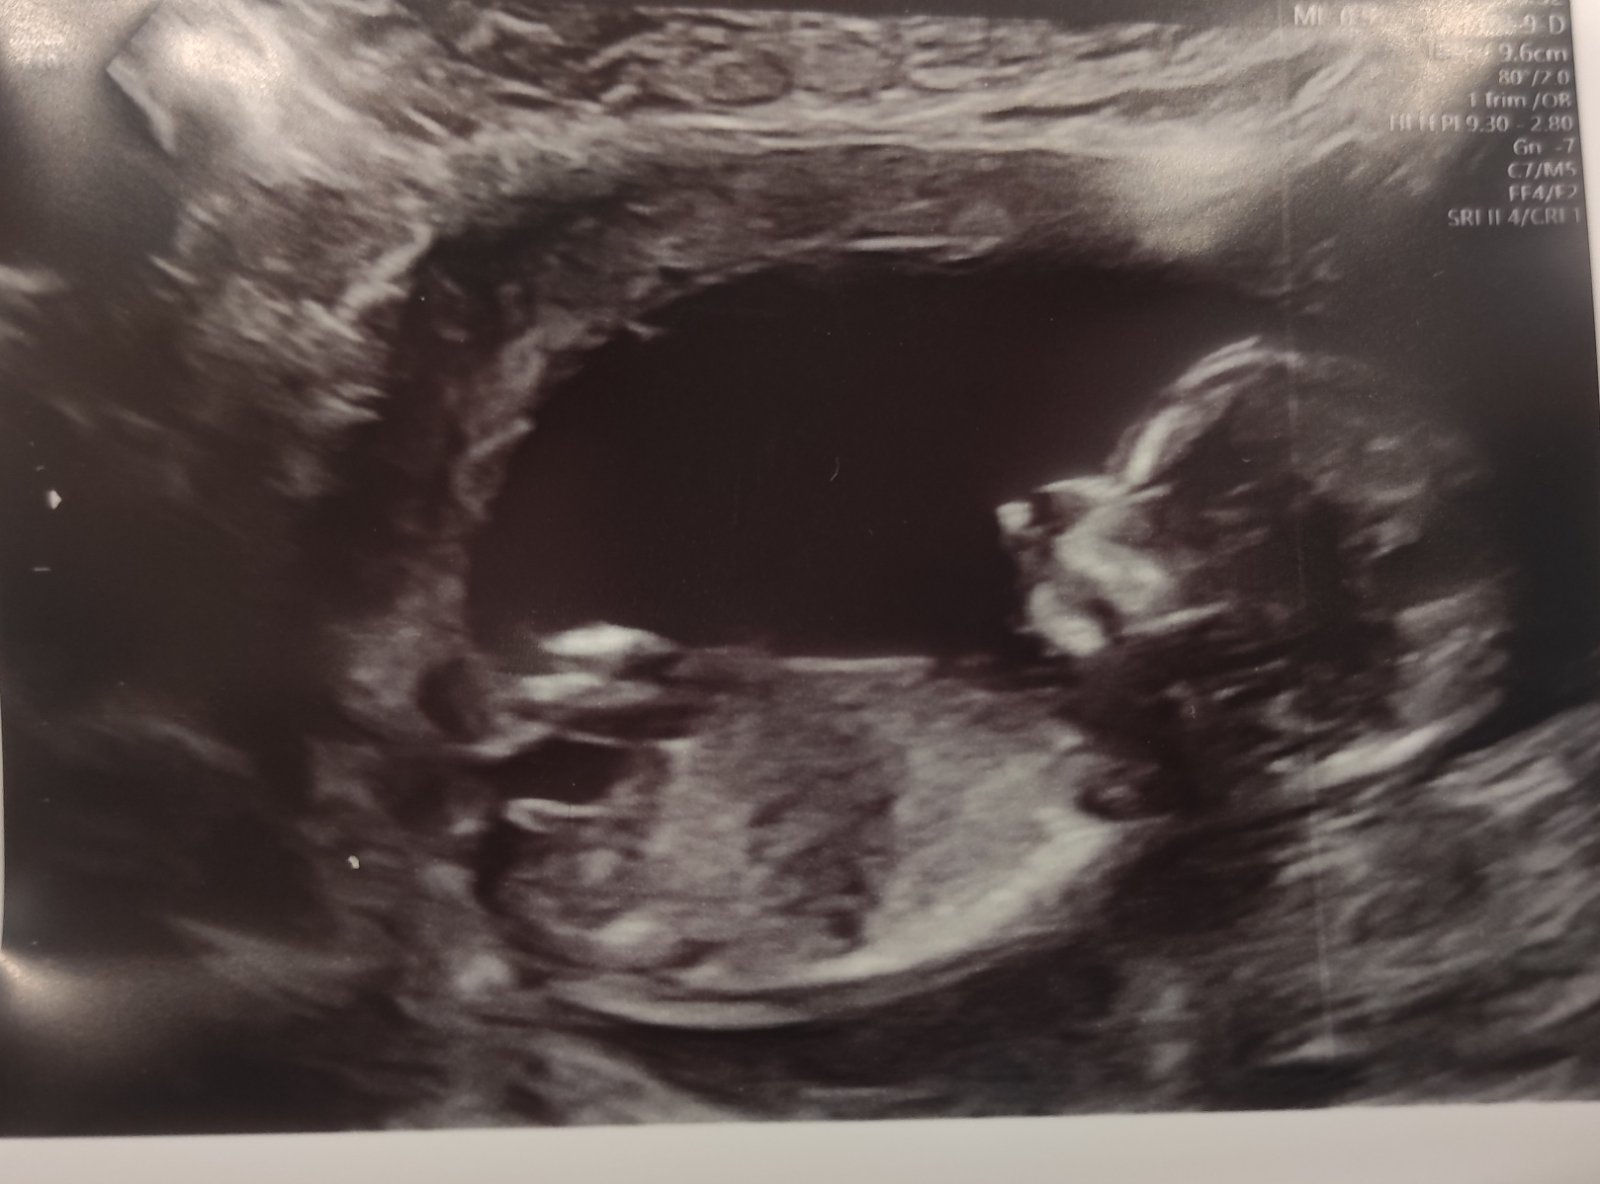

dokázal byste z této fotografie poznat, zda se jedná o holčičku či chlapečka?

Na screeningu v 14. tt mi vyšetřující lékařka řekla, že to vidí na chlapečka, ale já tedy, ať koukám, jak koukám, tak mi podle sklonu pohlavního hrbolku (pokud to, co vidím, je opravdu pohl. hrbolek) tedy vychází téměř ukázková holčička, a proto by mne zajímal i Váš názor.

posuzovat pohlaví z jednoho snímku a v prvním trimestru má své velké limitace a vždy je to jen hrubý odhad a dojem, ale máte pravdu, vypadá to spíše na holčičku. Stejně si počkejte na ultrazvuk ve 20. týdnu, tam to bývá již jednoznačné.